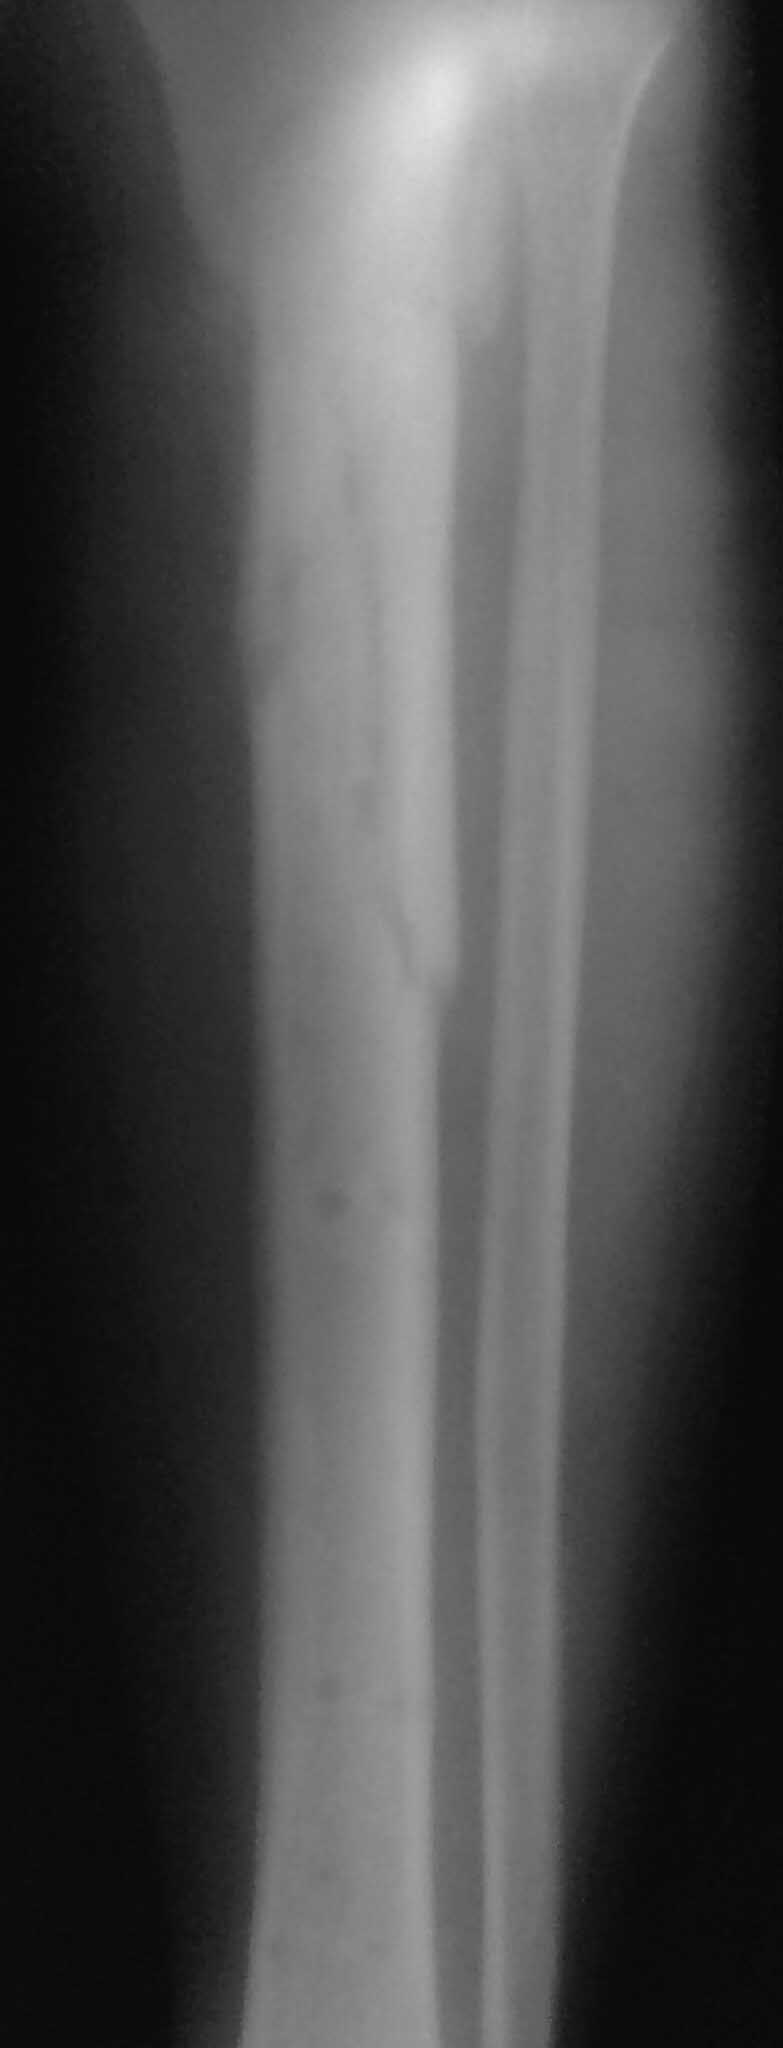

Все таки решились на штифт с антибиотическим покрытием. Выставляю R, в целом считаю неплохо вроде получилось.

Спасибо за обсуждение.Отправил остальные R, изиняюсь за качество.

Ни одного снимка, где было бы видно коленный сустав.. Не совсем понимаю столь яростное отрицание стержня, проксимальный отломок не так уж и короток, 3 разнонаправленных винта войти смогут. Учитывая продление на диафиз, если выбирать между здоровенной пластиной и стержнем, ИМХО целесообразнее стержень.